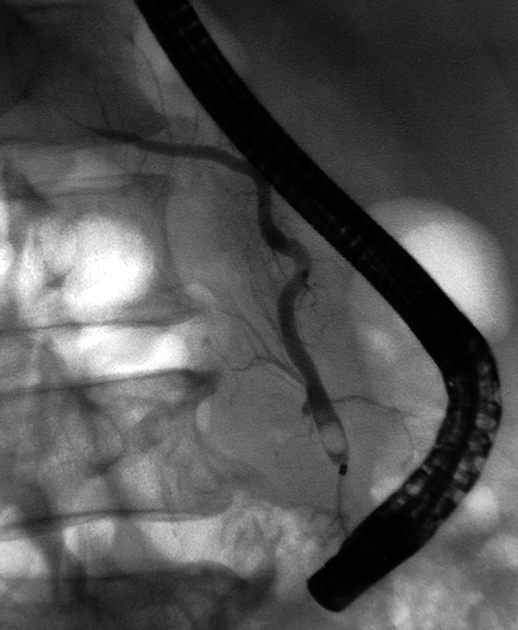

本性例のERCP画像では主膵管とその分枝にあきらかな狭窄所見や壁の不整を認めない。 膵には頭部(CT画像なし),尾部に腫瘤が形成されている。

腹腔内には静脈を巻き込むように血管周囲に腫瘤の形成がある。(クリックで大きな画像が見られます)